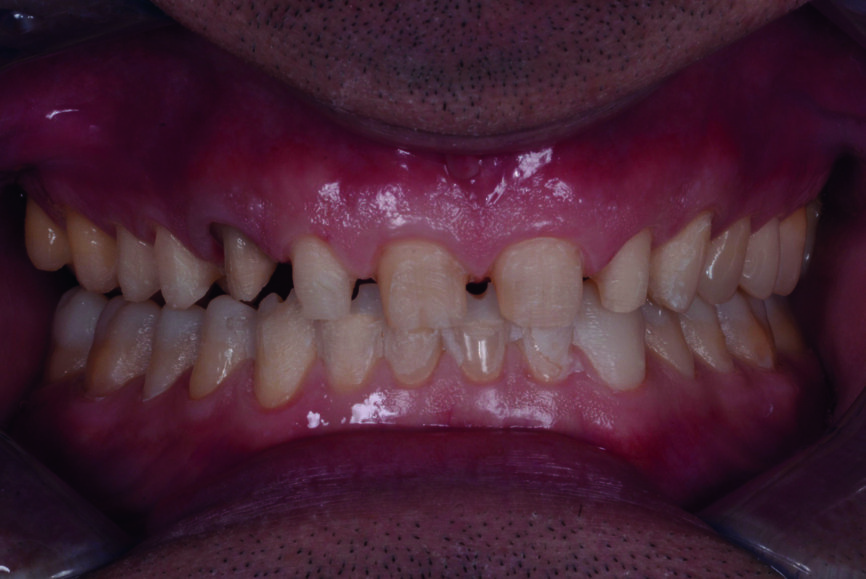

En 2015, un patient de 47 ans se présente au cabinet en raison d’une douleur au niveau de l’ATM. Il a également une préoccupation d’ordre esthétique, car une partie de la facette posée sur l’une des incisives centrales supérieures est fracturée (Figs. 1–3). L’analyse clinique et radiographique (Fig. 4) indique une perte de DVO et de substance dentaire dues au bruxisme.

Fig. 1 : Photographie intraorale avant le traitement, prise de face.